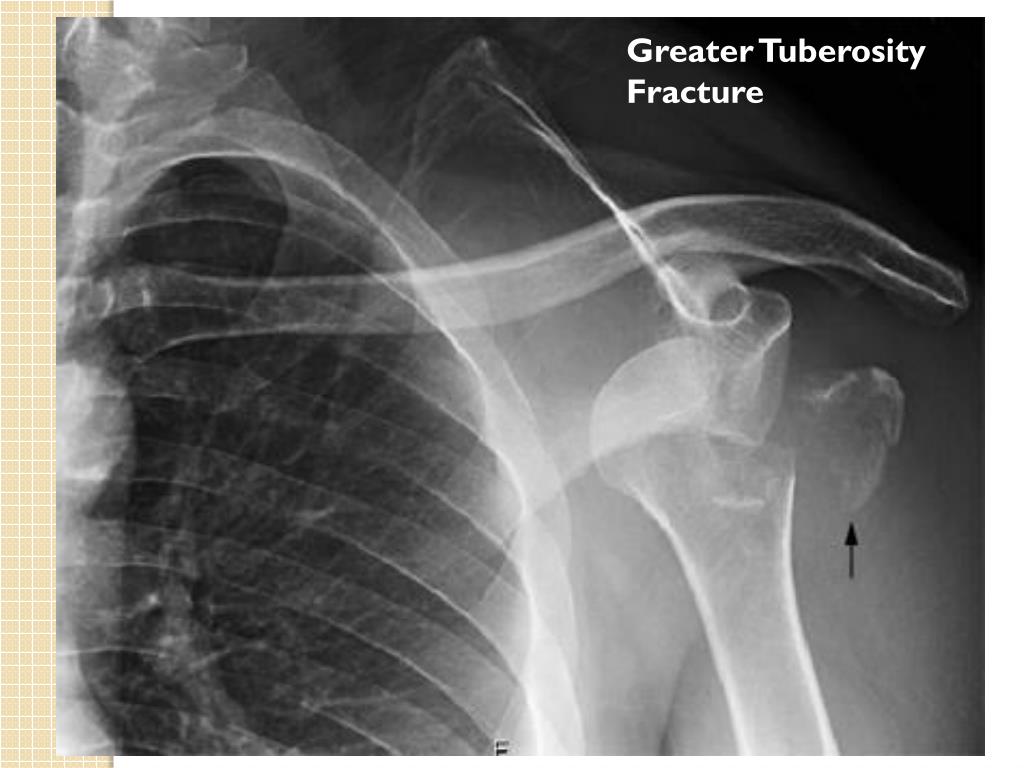

Shoulder X Ray Greater Tuberosity . The most common are avulsion injuries such associated with anterior shoulder dislocation, or direct trauma, as might occur in a fall on the shoulder or with. Radiographic findings of the shoulder joint have been reported in patients with rotator cuff tear, greater tuberosity changes are among. (a) frontal shoulder radiograph shows a complex fracture through the surgical neck with displaced humeral head and greater tuberosity. The american college of radiology recommends at least 3 views for acute traumatic shoulder pain [5]: Mistreated and unrecognized, these fractures can cause chronic pain and diminished shoulder range of motion and function. Ap in internal rotation for visualization of the lesser tuberosity. Scapula y or axillary view in place of true lateral. The diagnosis of glenohumeral dislocation is confirmed with at least two radiographic views of the affected shoulder. Greater tubercle fractures can be subtle and subsequently missed on initial radiographic imaging. Ap in external rotation for visualization of the greater tuberosity. Operative treatment options include open reduction and.

Shoulder X Ray Greater Tuberosity Greater tubercle fractures can be subtle and subsequently missed on initial radiographic imaging. Mistreated and unrecognized, these fractures can cause chronic pain and diminished shoulder range of motion and function. (a) frontal shoulder radiograph shows a complex fracture through the surgical neck with displaced humeral head and greater tuberosity. The american college of radiology recommends at least 3 views for acute traumatic shoulder pain [5]: Scapula y or axillary view in place of true lateral. Ap in external rotation for visualization of the greater tuberosity. The most common are avulsion injuries such associated with anterior shoulder dislocation, or direct trauma, as might occur in a fall on the shoulder or with. Operative treatment options include open reduction and. Radiographic findings of the shoulder joint have been reported in patients with rotator cuff tear, greater tuberosity changes are among. Greater tubercle fractures can be subtle and subsequently missed on initial radiographic imaging. Ap in internal rotation for visualization of the lesser tuberosity. The diagnosis of glenohumeral dislocation is confirmed with at least two radiographic views of the affected shoulder.